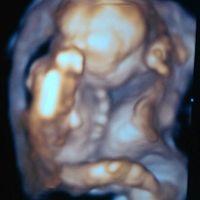

3073 giorni faBuongiorno mammine e future mammine.... all'ultimo controllo,dove abbiamo scoperto anke ke avremo un bel maschietto,il nostro ginecologo ci ha fatto l'ecografia in 3D.... è stupendo. Vederlo e sentirlo e ogni volta una grande emozione....nn vedo...